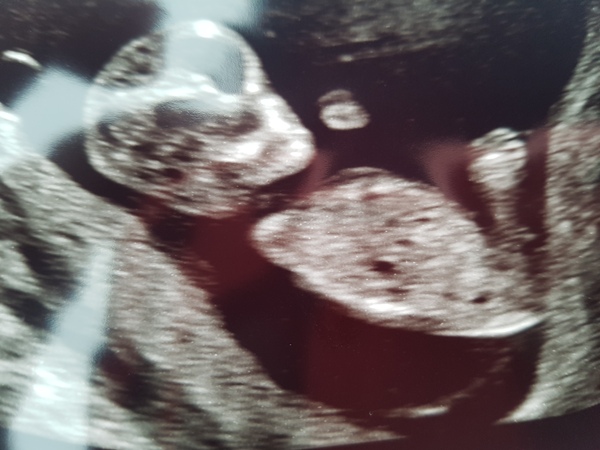

abbeyb123 · 10/02/2018 22:03

This is mine 😃